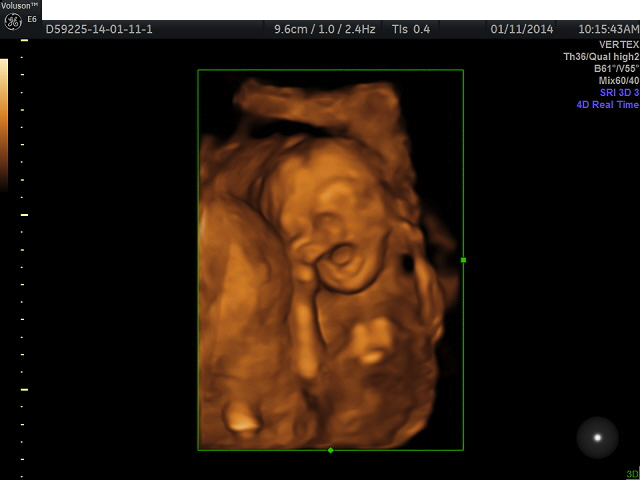

It's a boy! We did an elective early gender reveal this morning. There is no denying that we're team blue. Now we can have fun with brainstorming names....

We went to a place that did 3d ultrasound. It was so amazing and would recommend it to anyone. Our baby boy was moving all around the place. Super active, which explains all the kicks I've been feeling already.

I attached a picture of the baby yawning.